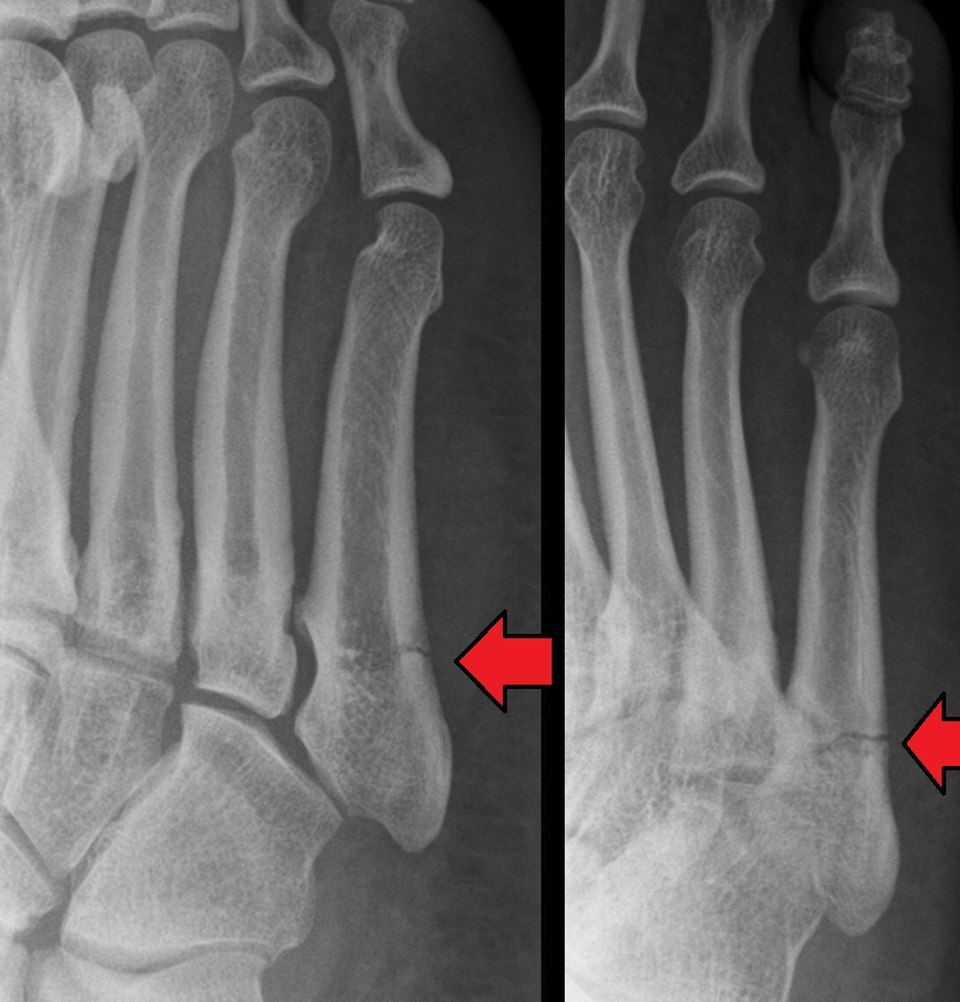

JONES

- Transverse fracture of the fifth metatarsal base, occurring at least 15 mm distal to the proximal end of the bone, distal to the insertion of the peroneus brevis

How well did you know this?